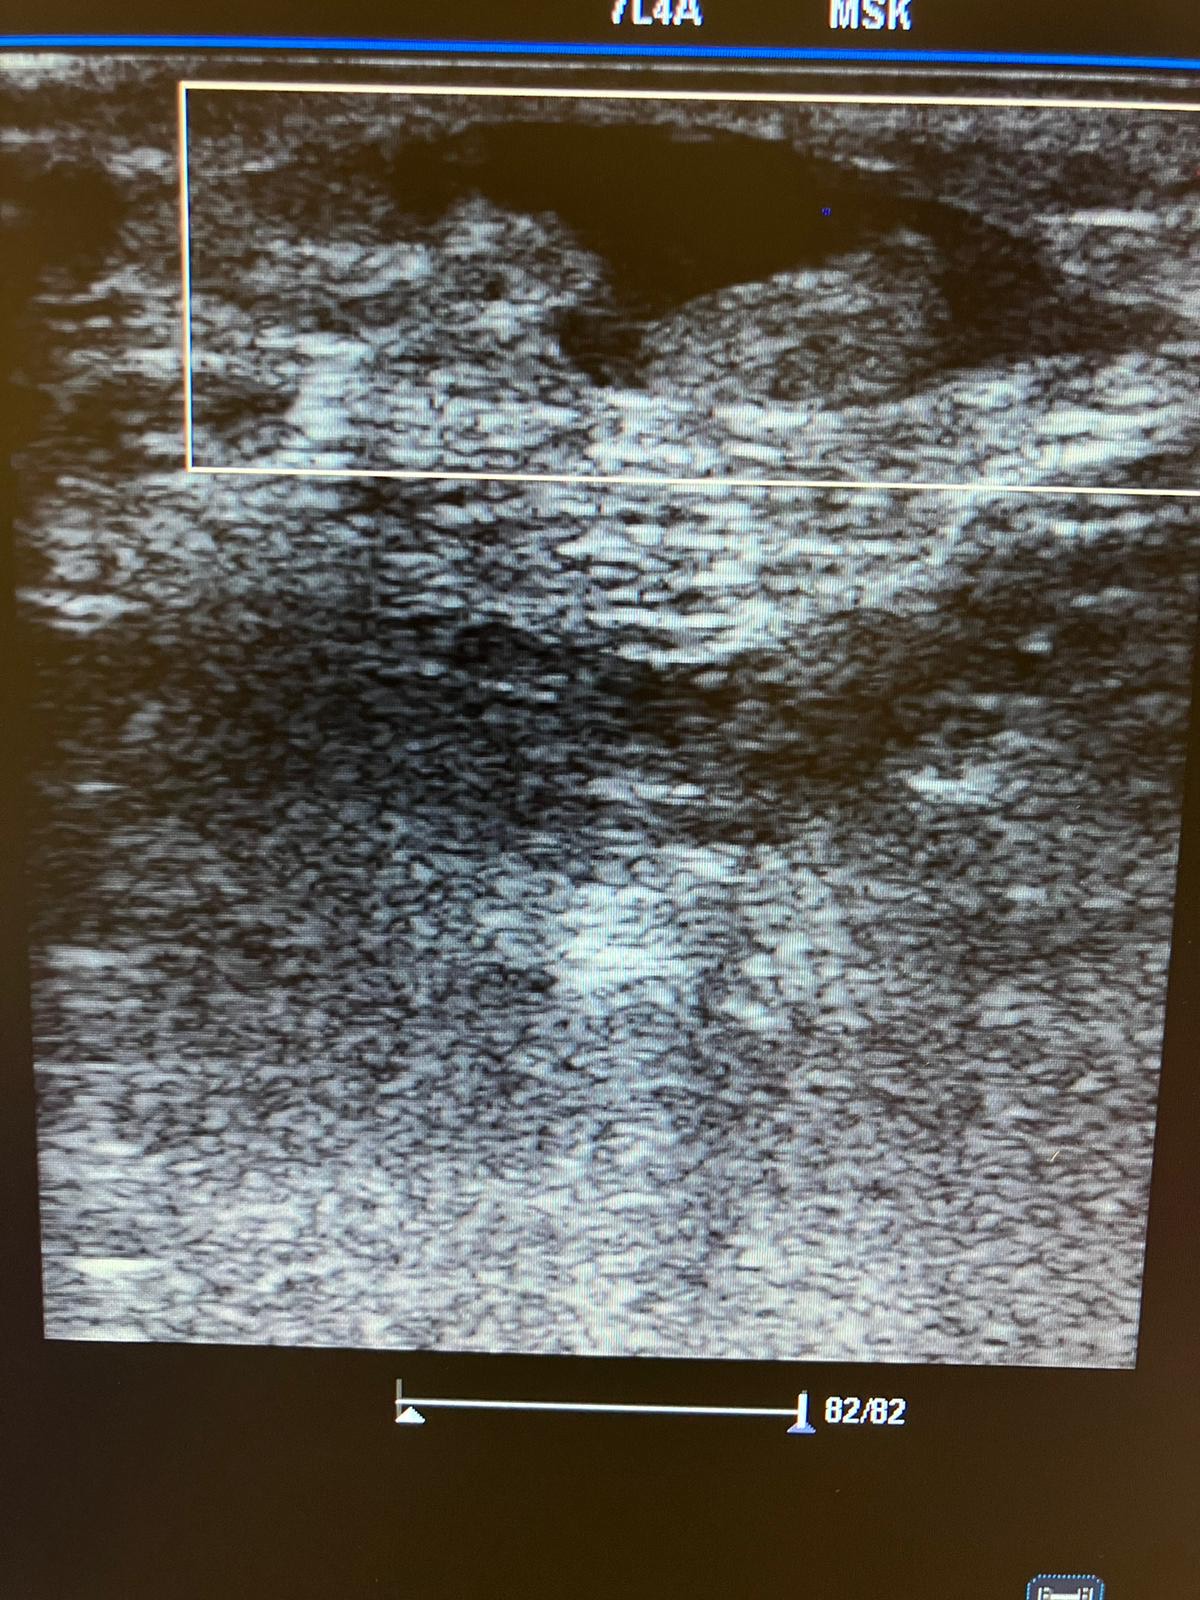

Insonación: pequeña colección líquida con colecciones hipercaptantes en su interior, no captan Doppler color ni Doppler pulsado. Venas poplíteas sin signos de TVP.

Mejoría del eritema a los 5 días con menor edema de la pierna. Lo volvimos a valorar a los 10 días encontrándose mucho mejor, ya sin edema ni eritema. En la insonación, persistía misma imagen al inicial hace 10 días, compatible con sero-hematoma de Morell Lavallé.